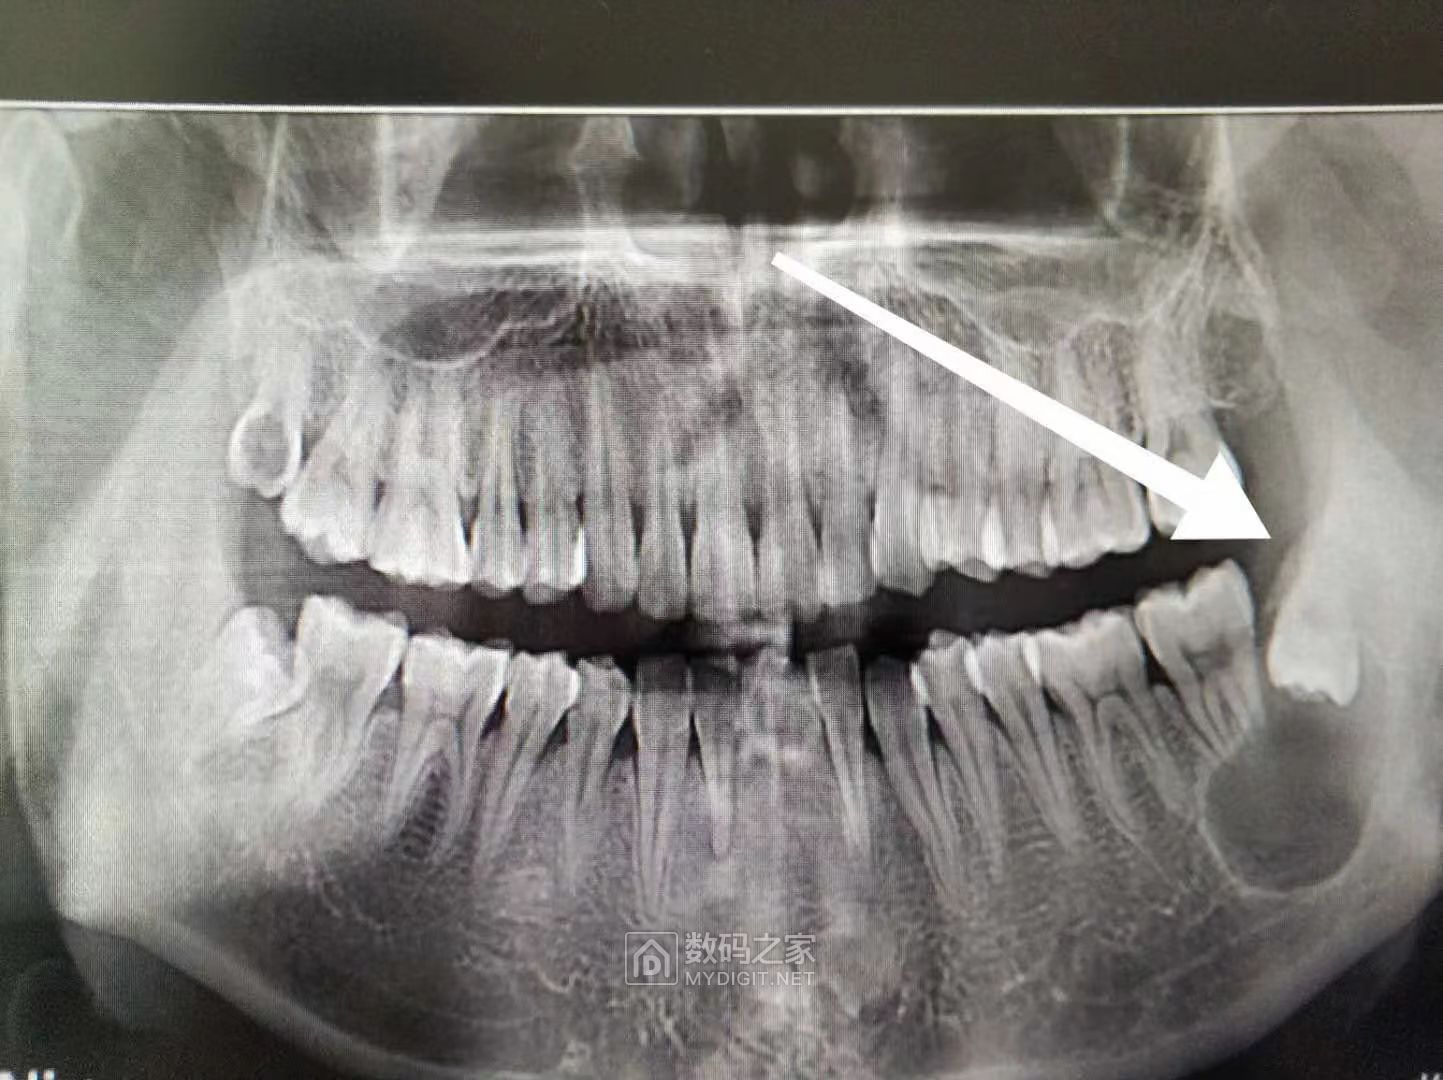

自己开车出去吃饭?你太厉害了,我手术完出来脸肿得像大馒头,胸口气管疼的厉害,这是我的其中一张CT

哈哈,和我的简直一模一样,我是到诊所拔智齿拍牙片发现另外一边有个智齿倒长带着囊肿,大夫就说很难搞要到大医院处理,费用过万,  拖了一年下决心搞了,也是要全麻且住院,为了住院不麻烦家里人伺候,就选了老家附近的区人民医院,从市里人民医院请专家过来坐手术,私下给红包,  不到一上午搞定,然后自己全麻醒了以后没什么事后家里人都回去了,就自己一个人住院,住了7天,反正每天挂完水之后自由活动,到饭点了,自己开车出去吃饭再回来,费用大概1.3W+2000k专家费,真心肉疼啊,最后把刀口里的纱布取出来 麻药都不管用,硬拉出来再封上,哎 往事不堪回首

土豆有大有小,直径多少?

elamd + 6 最大截面积3.8X3.8cm